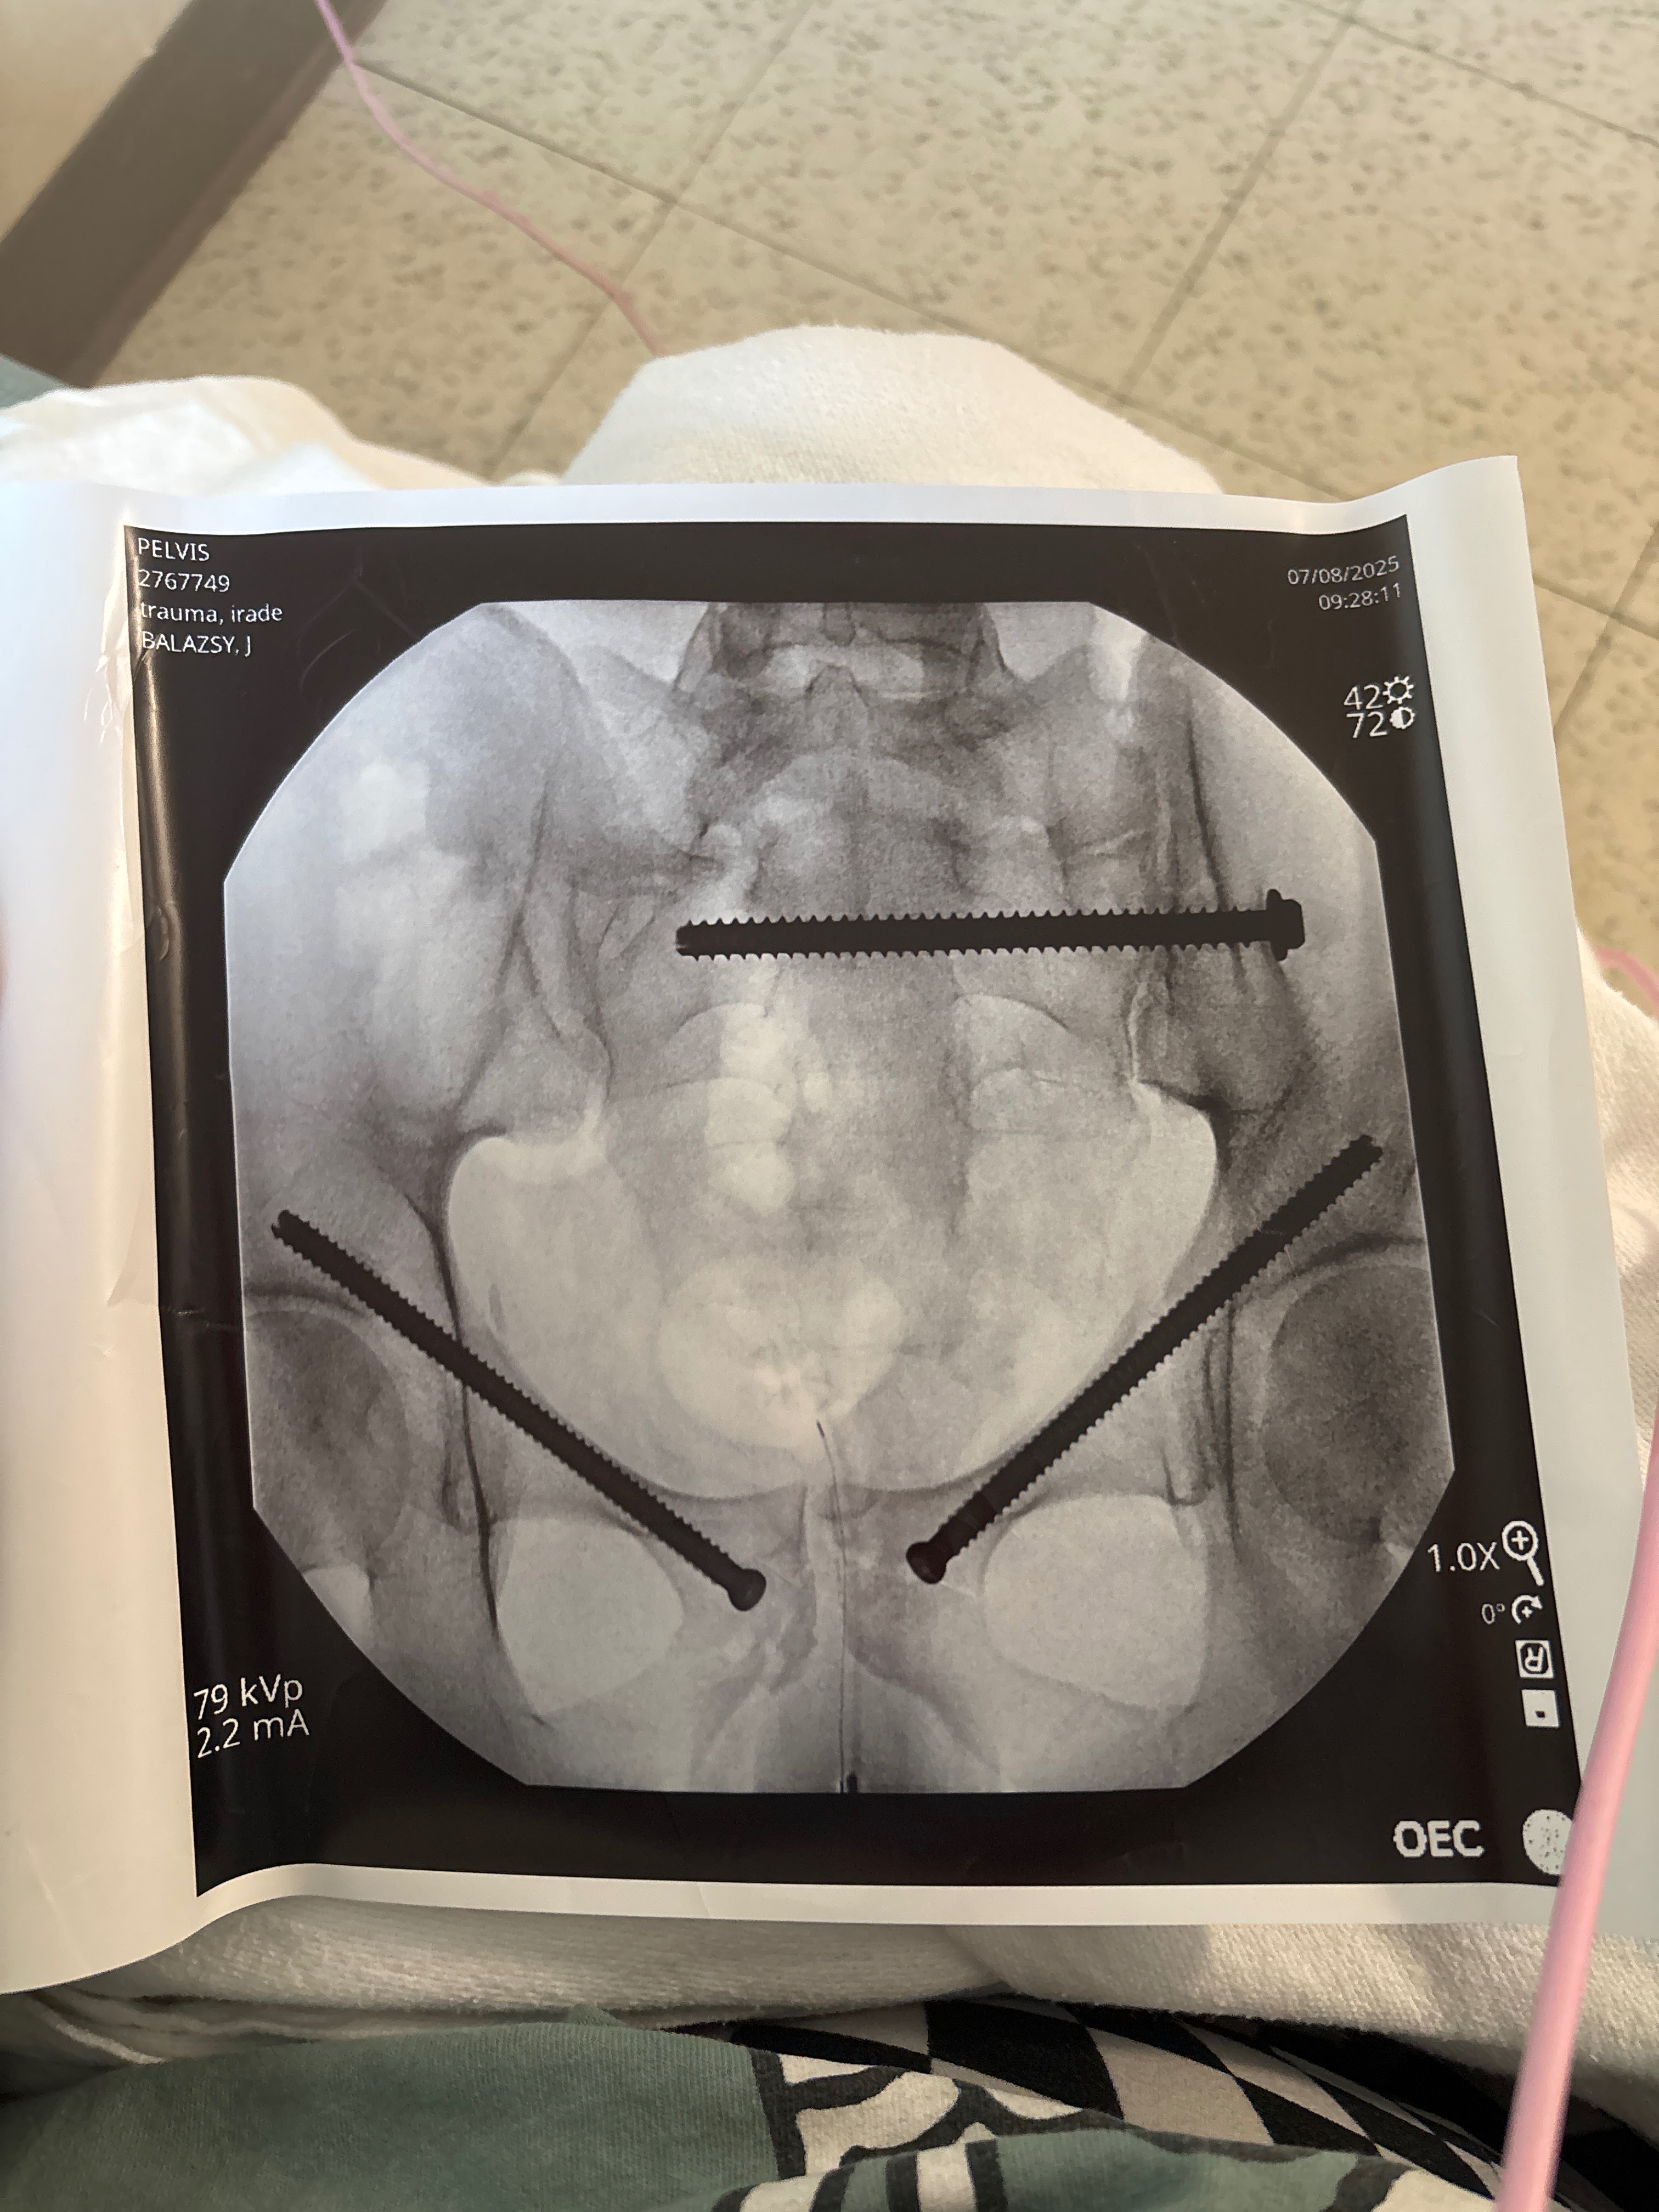

- My name is Libbie, I am Rylands older sister. This morning around 2-2:30am, my brother was in a hit and run on Allison Avenue. He was walking home, literally on his street, when we suspect he was beaten and there in the road where he was ran over. There’s a lot we are being told/not told. He is currently laying in the ICU with several skull fractures, a broken pelvis that is reattached by 3 larger screws, a broken jaw, draining fluid from his head, plus a body full of stitches and sutures. In the morning at 7am, he is scheduled for a frontal craniotomy to scrape and clean it out to help prevent future infections such as meningitis, etc.